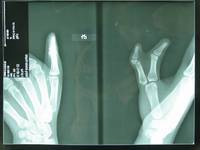

多數(shù)多指行X線檢查,明確其骨關(guān)節(jié)情況,為手術(shù)提供依據(jù)。